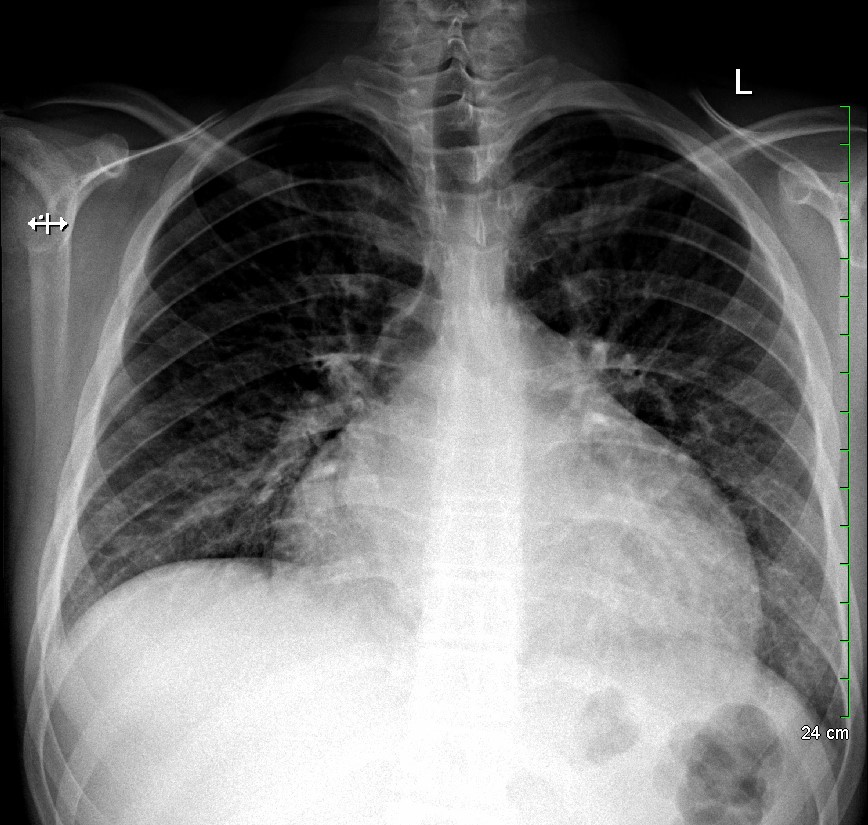

KUB read as normal by radiology. However, because of the enlarged heart border found incidentally on KUB, troponin I (0.05 ng/mL), B-type natriuretic peptide (BNP) (2186 pg/mL), and chest x-ray (CXR) was obtained, which showed the following:

With cardiomegaly confirmed, it was determined that the patient was in heart failure, and that his symptoms of abdominal pain and vomiting were likely the result of abdominal insufficiency. Cardiology performed an echocardiogram, which showed dilated cardiomyopathy, severely reduced systolic function, and a left ventricular ejection fraction of 10-15%. The patient was transferred to a cardiac surgical center for heart transplant.